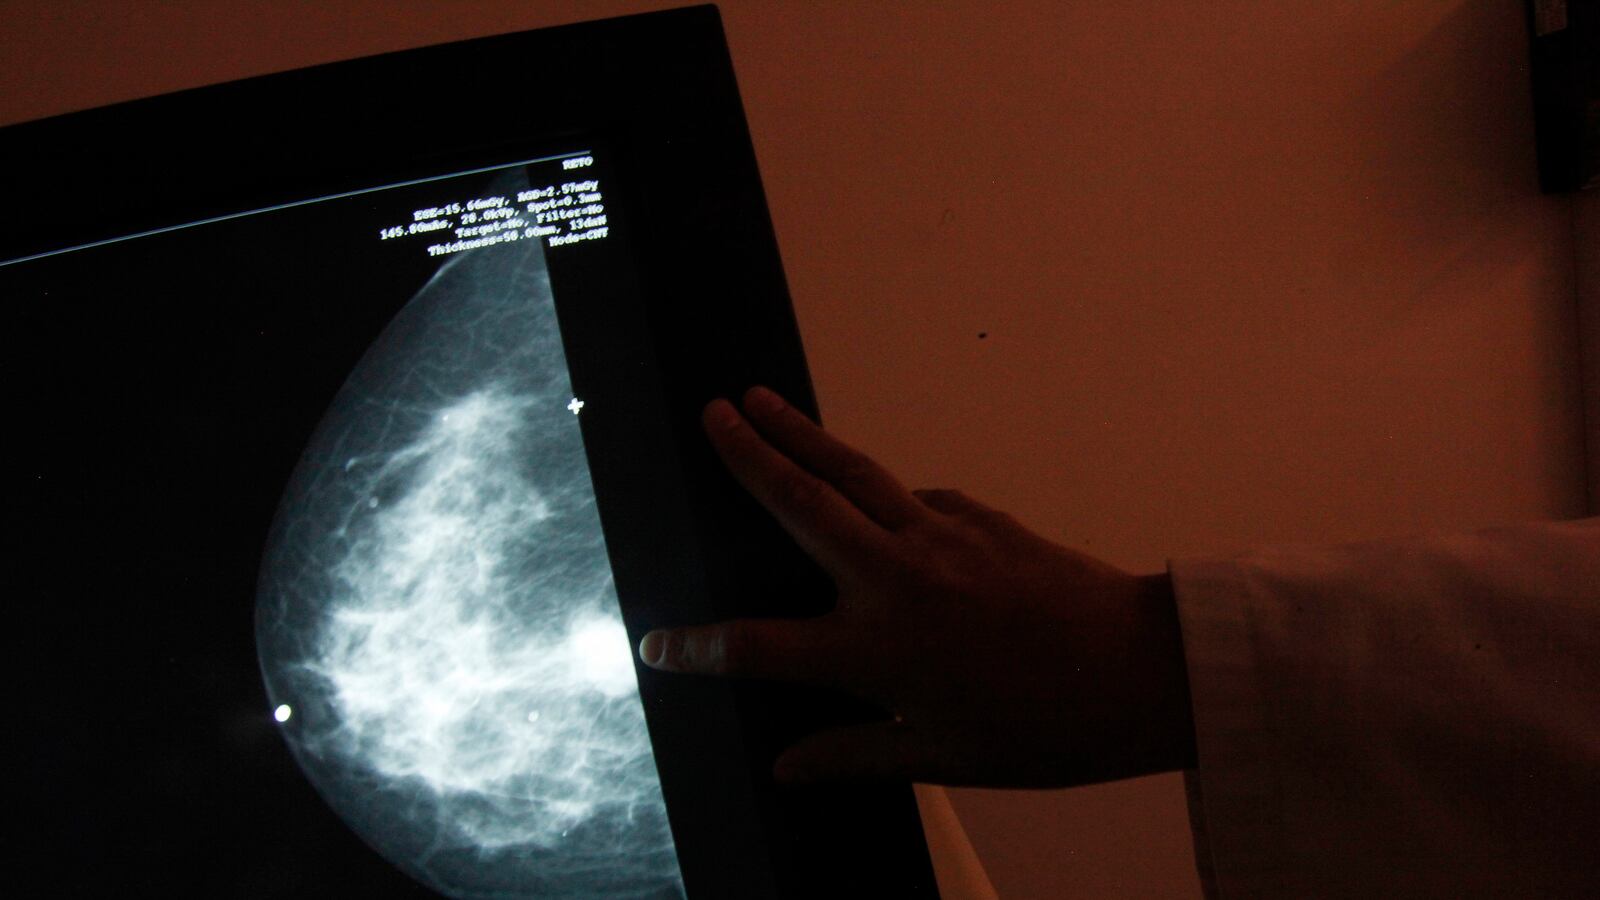

A federal task force is now recommending that people take their ancestry into consideration when deciding whether to get screened for genetic mutations linked to breast cancer—guidance that appears to be aimed at Ashkenazi Jews. Studies have shown that one in 40 Ashkenazi Jews have one of the BRCA1 or BRCA2 mutations, compared with one in 300 people in the general population. The recommendation published in the Journal of the American Medical Association does not specify which ancestry should think about getting tested, but the task force is certainly referring to Ashkenazi Jews, who are disproportionately affected by the mutations.